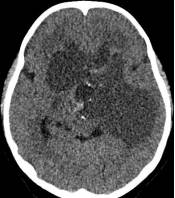

鉴于肿瘤体积超大,而且患儿间断出现意识障碍,直接作手术完全切除肿瘤的难度很大,为降低手术风险,所以我们采用先穿刺肿瘤囊减少肿瘤体积,降低颅压,二期手术争取完全切除肿瘤的策略。行肿瘤囊肿穿刺后,引流出约100多毫升囊液,肿瘤体积显著变小,见图3、图4。

图4.肿瘤囊穿刺手术后肿瘤体积减小

白色箭头示引流管